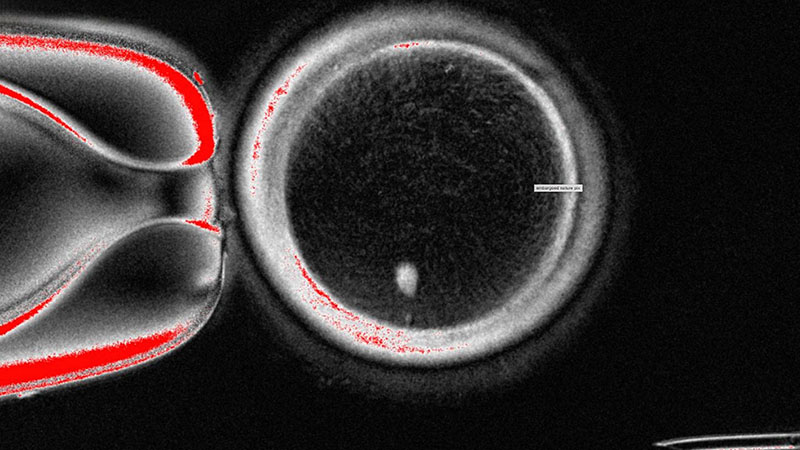

The OHSU team, led by Shoukhrat Mitalipov, removed the nucleus from a human egg cell and replaced it with the nucleus from a skin cell. This innovative approach encountered complications since skin cells contain two sets of chromosomes, while eggs and sperm should each only contain one set. To address this, the researchers induced the egg-like cells to discard the extra chromosomes, subsequently injecting donated sperm to initiate post-fertilization development.

Of the generated cells, approximately 9% survived for six days in laboratory conditions, reaching the blastocyst stage of early embryo development before the experiment was halted. Despite these advancements, the primary concern arose from observed chromosomal abnormalities that hindered the potential of these cells to form genetically normal embryos or eggs.